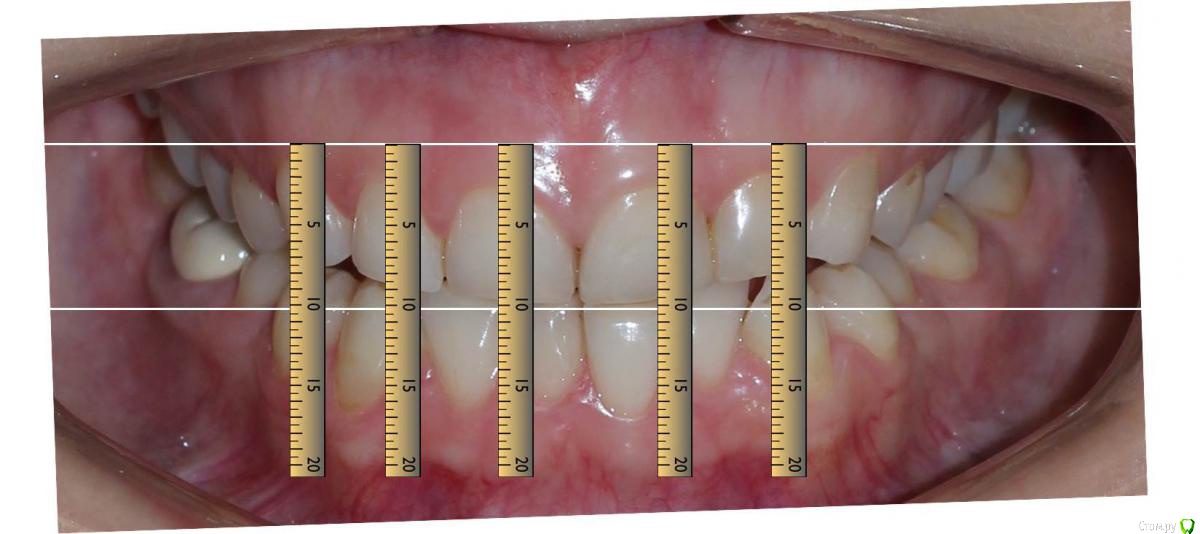

Сева северный Опубликовано 11 декабря, 2015 Автор Поделиться Опубликовано 11 декабря, 2015 (изменено) Как вы определяете когда надо делать хир.удлинение коронки, а когда просто удлинить без хирургии. По стертым режущим краям,похоже что не было нарушения прорезывания...зондировали до ЦЭС? Или по десневой улыбке скромной решили пойти апикально?Я сделал только планирование.... Ход мысли был следующий: Длина центральных резцов 19-20 мм. Длина коронковой части зуба центрального резца 7-8 мм. Оптимальная длина 10.5. По результату пациентка с мотивирована на ортодонтию , с коррекцией gammy smile. Решение по хирургии, примем по результатам ортодонтии. Изменено 11 декабря, 2015 пользователем Сева северный 1 Ссылка на комментарий

Сева северный Опубликовано 10 декабря, 2015 Автор Поделиться Опубликовано 10 декабря, 2015 Достойно.А можно рентген зубов,посмотреть соотношение корень коронка.Пациентка, реферативно, от ортодонта. Резцы короткие около 19 мм. Ссылка на комментарий